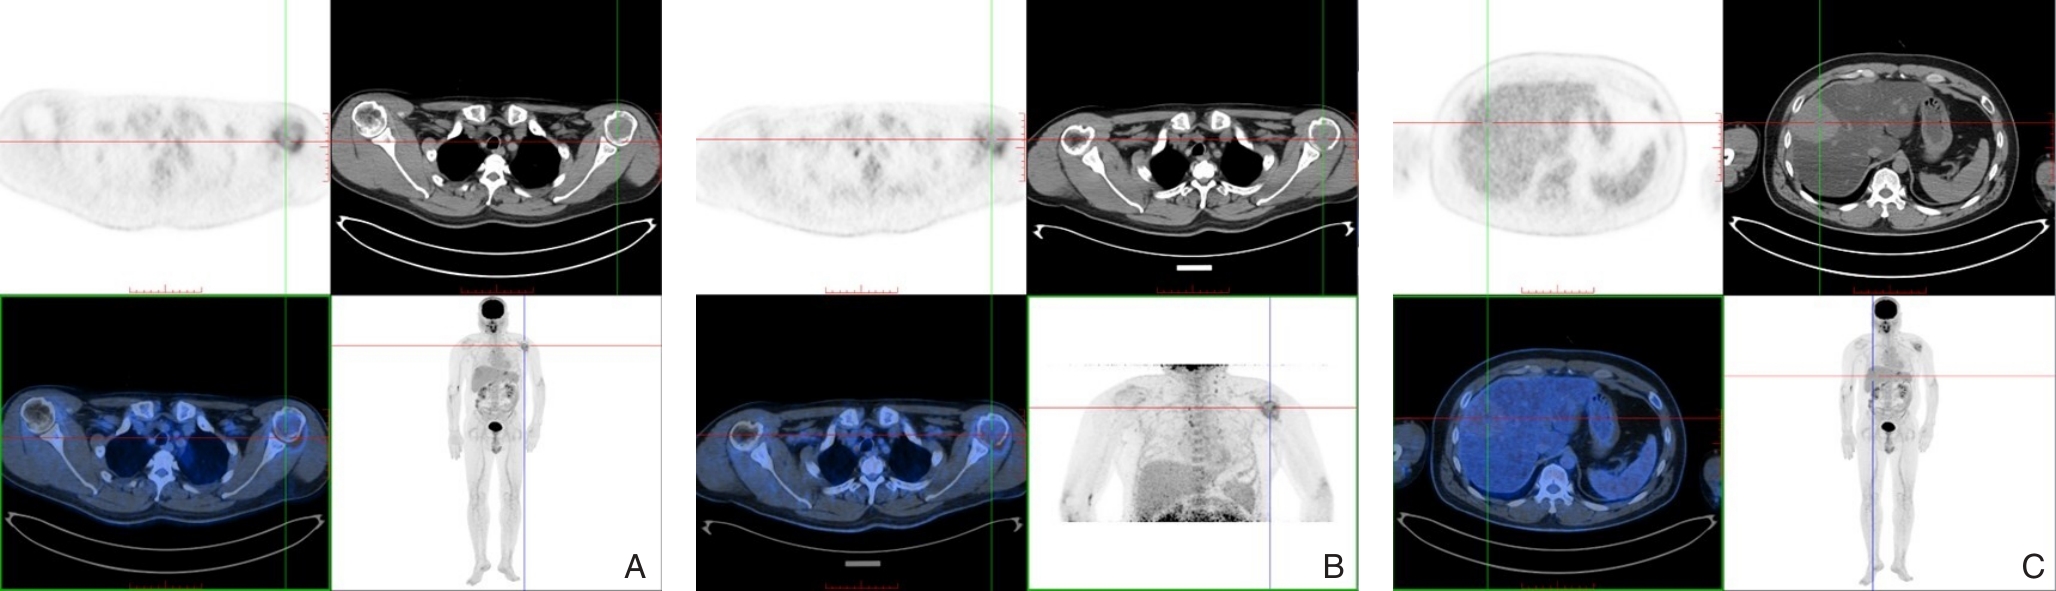

Background and Aims Hepatocellular carcinoma (HCC) presenting initially with bone metastasis is uncommon, and metastasis to the appendicular skeleton is particularly rare. These cases often lack typical liver disease history, elevated alpha-fetoprotein (AFP), or characteristic imaging findings, leading to frequent misdiagnosis or delayed diagnosis. This study reports a rare case of occult HCC presenting with humeral metastasis and reviews the literature to improve clinical recognition and management.Methods The clinical data of a 42-year-old male patient presenting with humeral metastasis as the initial manifestation admitted in August 2025 were retrospectively analyzed, including laboratory tests, multimodal imaging findings, histopathological and immunohistochemical results, treatment, and follow-up outcomes. Relevant literature was also reviewed.Results The patient presented with left shoulder pain. Imaging revealed osteolytic destruction of the left humerus. PET/CT incidentally detected multiple hepatic lesions without significant FDG uptake. Contrast-enhanced ultrasound demonstrated atypical enhancement patterns, initially suggesting a perivascular epithelioid cell tumor. Histopathological and immunohistochemical examination of biopsy specimens from both the humeral and hepatic lesions confirmed moderately differentiated hepatocellular carcinoma with humeral metastasis (CNLC stage IIIb). The patient received systemic therapy with sintilimab plus bevacizumab, followed by transcatheter arterial chemoembolization. After 6 months of follow-up, the intrahepatic lesions had decreased in size, the bone metastasis remained stable, and pain symptoms were significantly relieved.Conclusion HCC presenting with humeral metastasis as the initial manifestation is extremely rare and may lack typical imaging and serological features. Clinicians should consider HCC in patients with unexplained bone metastasis even in the absence of liver disease history or elevated AFP. Multimodal imaging and pathological biopsy are essential for accurate diagnosis and appropriate management.